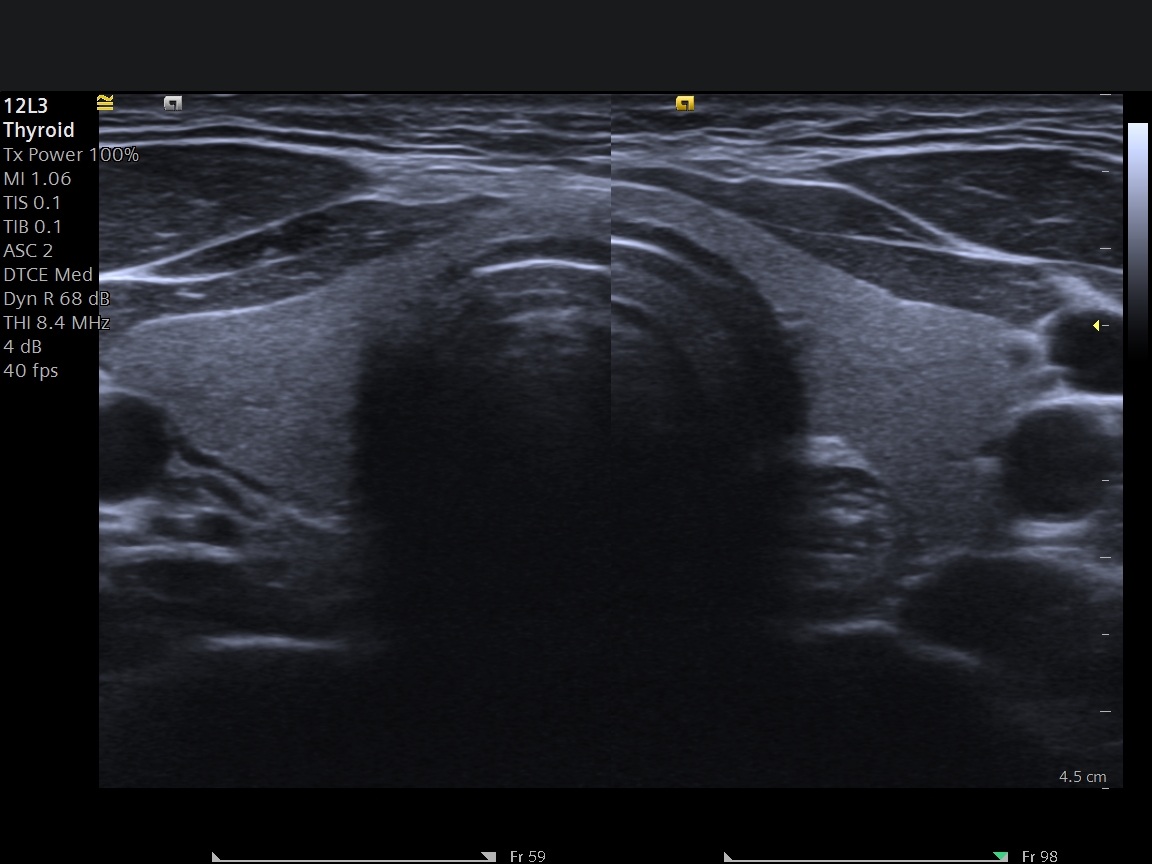

Ultrasonografi yaygın klinik kullanımı ve gündelik sorunlara pratik çözümler sunan bir modalite olmakla birlikte elde edilen bulgular hem uygulayıcıya bağımlı hemde kullanılan cihazın teknik özellikleri ile ilişkilidir. Merkezimizde 2024 model Siemens Acuson Juniper cihazımızla 20 yıldan fazla tecrübeli Avrupa radyoloji Diplomasına sahip (EDIR) hekimlerimiz tarafından incelemeleriniz yapılır. Merkezimizde her hastaya yeterli zaman en az 20 dk ayrılarak detaylı incelemeler gerçekleştirilir.

Tiroid Ultrasonografisi